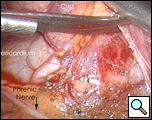

手術室では、全身麻酔と一つの肺換気の下で、胸腔鏡が右中顎線と第7肋間腔に導入された(下のビデオ1)。 嚢胞は、約9x6cmを測定し、右心膜の前外側の側面で容易に視覚化された(図3)。 嚢胞の後方に横隔神経を認めた。 第4肋間腔の前腋窩線に第二の切開を行った。 リングクランプを用いて嚢胞を把握した(図4)。 第5肋間腔の肩甲骨ラインに第三の切開が行われた。 胸腔鏡下はさみと焼灼術(心臓不整脈の可能性を最小限に抑えるために低い設定で)は、心膜から嚢胞を解剖するためにそのポートを介して使用された(図5)。 嚢胞と心膜腔との間の接続が同定された。 それは小さく、はさみで分割されました。 嚢胞の後面の解剖により除去が完了した。 横隔神経は常に明瞭に視覚化されていた。 病理報告では、良性の中皮内嚢胞の診断が確認されました(図6)。

| 図3.:心膜嚢胞の術中所見。 | 図4。 心膜嚢胞のリングクランプ収縮。 |

| 図5. 横隔神経を視野に入れた嚢胞切除術を施行した。 | 図6。 切除標本 |